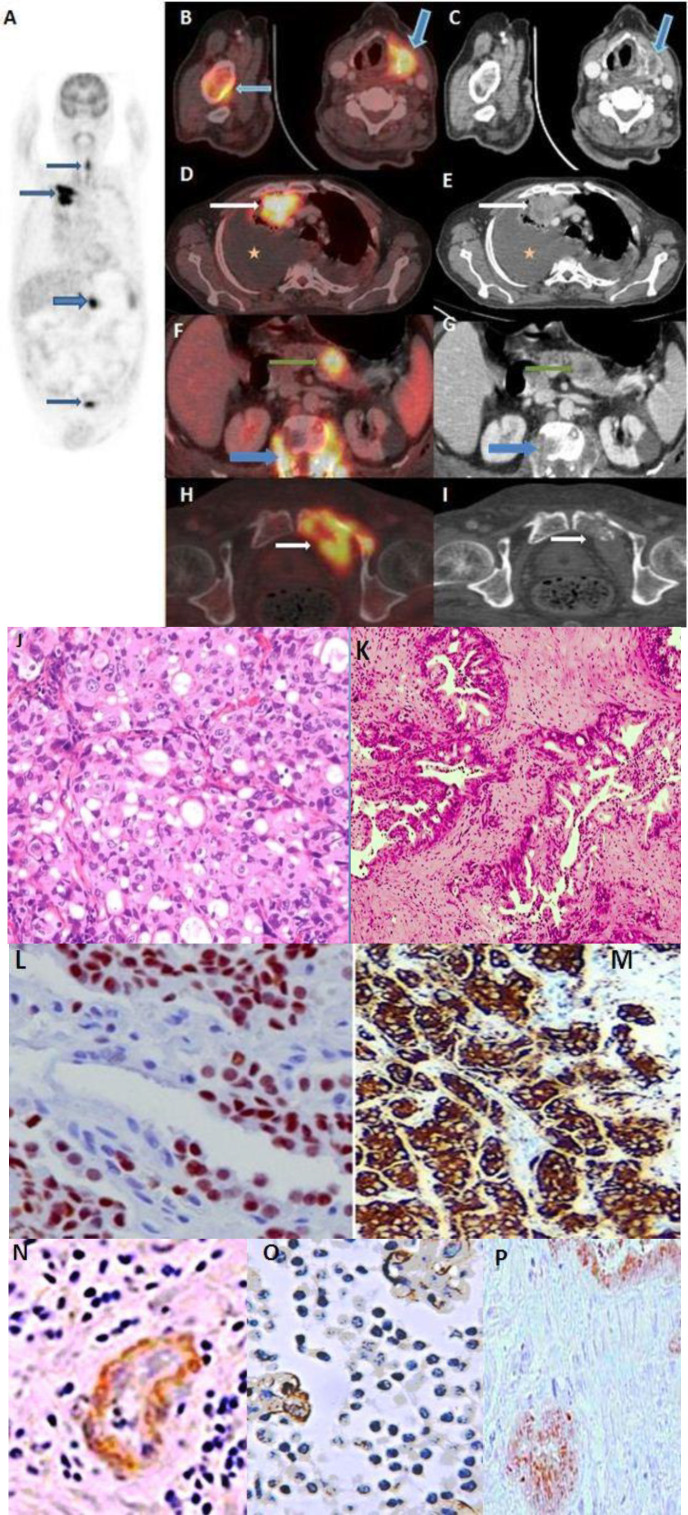

Results: On whole body 18F-FDG PET/CT, distant metastases were detected in 33 (11.7%) patients, all with locally advanced primary tumors corresponding to T category 3 and 4. Lung (6%) and bone (~6.7%) were the most common sites of distant metastasis. In nine patients metastases were detected below the diaphragm. Synchronous malignancies were discovered and histopathologically proven in 22 (7%) patients. Lung carcinoma was the most common synchronous tumor, detected in 9 patients. In seven patients synchronous tumour was detected outside the aerodigestive tract, of which four were below the diaphragm.

Conclusions: Of the distant metastasis diagnosed in 11.7% of HNC patients with TNM tumor category T3 and T4, 3% of metastasis lesions were detected below the diaphragm. Synchronous malignancy was diagnosed in 7% patients irrespective of primary HNC stage. These findings demonstrate the advantage of using whole body 18F-FDG PET/CT as an ideal and preferred modality for initial staging and screening of HNC patients since detection of distant metastasis or a synchronous malignancy changes the management approach in these patients.